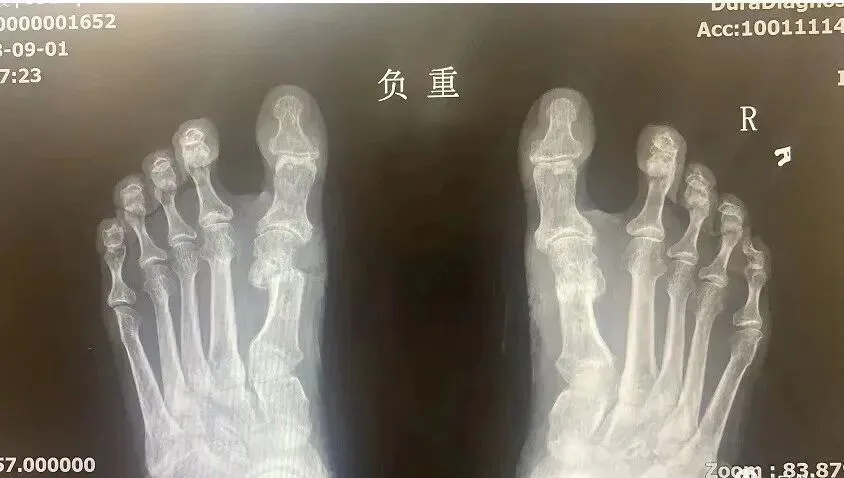

术前术后X光片对比图

术后X光片参考